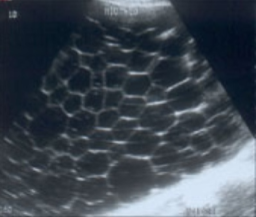

echinococcal cyst

echinococcal cyst (squiggle lines is the water lily sign)